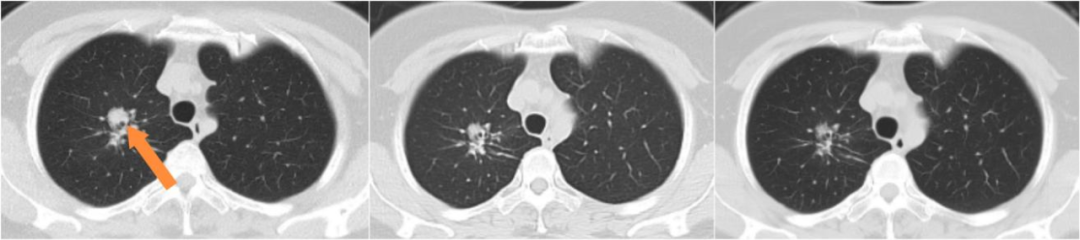

患者女,54岁,2023年11月因咳痰带血,检查肺增强CT提示右肺上叶占位,气管镜检查右肺上叶B2支气管新生物取病理,病理诊断为肺腺癌,基因检测结果:EGFR21L858R突变、TP53突变、BTK突变、ERBB2突变、KRAS扩增、TPS=60%。PET-CT提示右肺上叶肿块考虑恶性,右侧锁骨上、纵隔及右肺门淋巴结转移,临床分期为cT2aN3M0 IIIB期,PS评分1分。患者拒绝根治性放化疗,于2023.12月行伏美替尼80mg治疗,期间每2月复查评效PR,2024.8月复查肺CT肺内病灶增大提示疾病进展,PFS1=8个月;2024.8月行贝伐珠单抗联合AP方案4周期,贝伐珠单抗联合培美曲塞8周期维持治疗,2、4、6、8、10周期评效PR,2025.4月右肺上叶病灶持续增大评效PD,PFS2=8个月;2025.4月行依沃西单抗联合PC方案治疗4周期,依沃西单抗联合培美曲塞维持治疗4周期,2、4、6、8周期评效PR,PFS3超过5个月治疗持续有效中,药物安全性良好,未见相关不良反应发生。

依沃西单抗8周期疗效对比